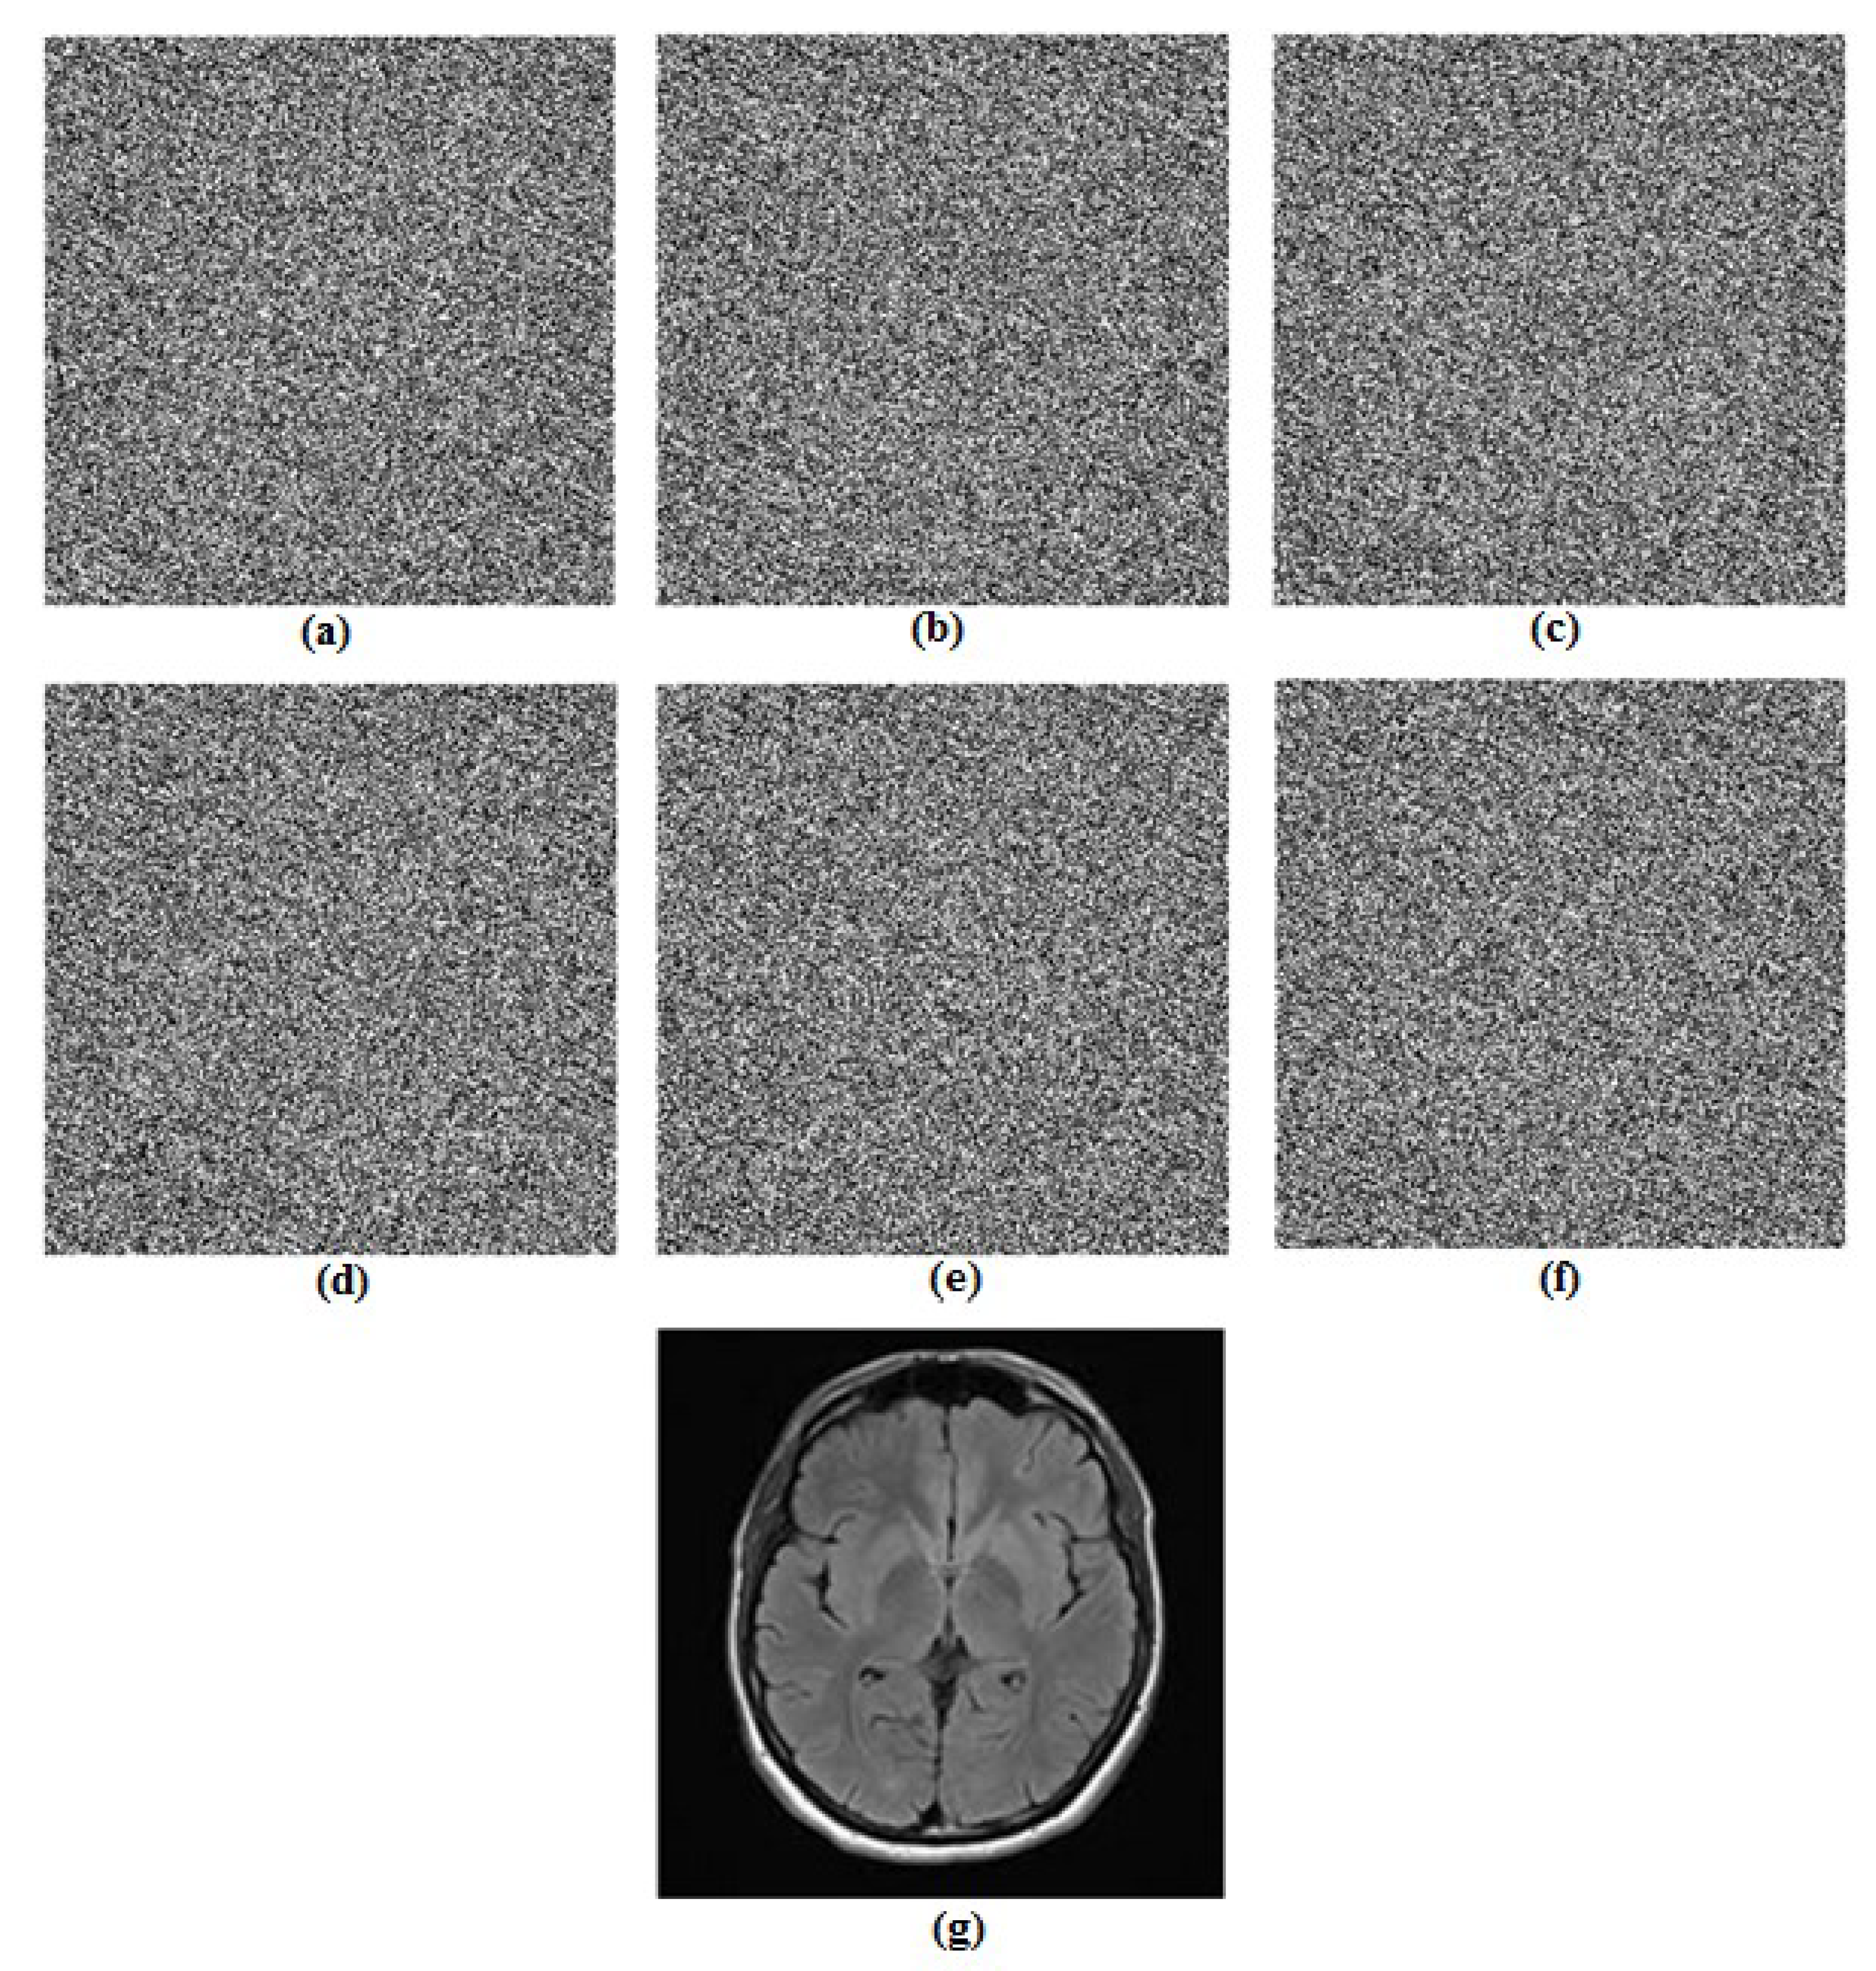

5.3.2. Key Sensitivity Analysis

5.3.3. Information Entropy